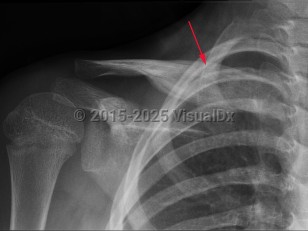

Chronic recurrent multifocal osteomyelitis (CRMO) is a rare nonbacterial cause of osteomyelitis. It is an autoimmune inflammatory disorder that causes multi-site, relapsing bone inflammation in the absence of typical infectious causes. Patients present with bone pain, swelling, and decreased mobility. CRMO most often occurs in children. CRMO sometimes co-exists with other autoimmune diseases such as inflammatory bowel disease or within a genetic syndrome. Nonsteroidal anti-inflammatory drugs (NSAIDs), corticosteroids, and bisphosphonates have all been used to treat CRMO. The disease typically has a relapsing and remitting course.